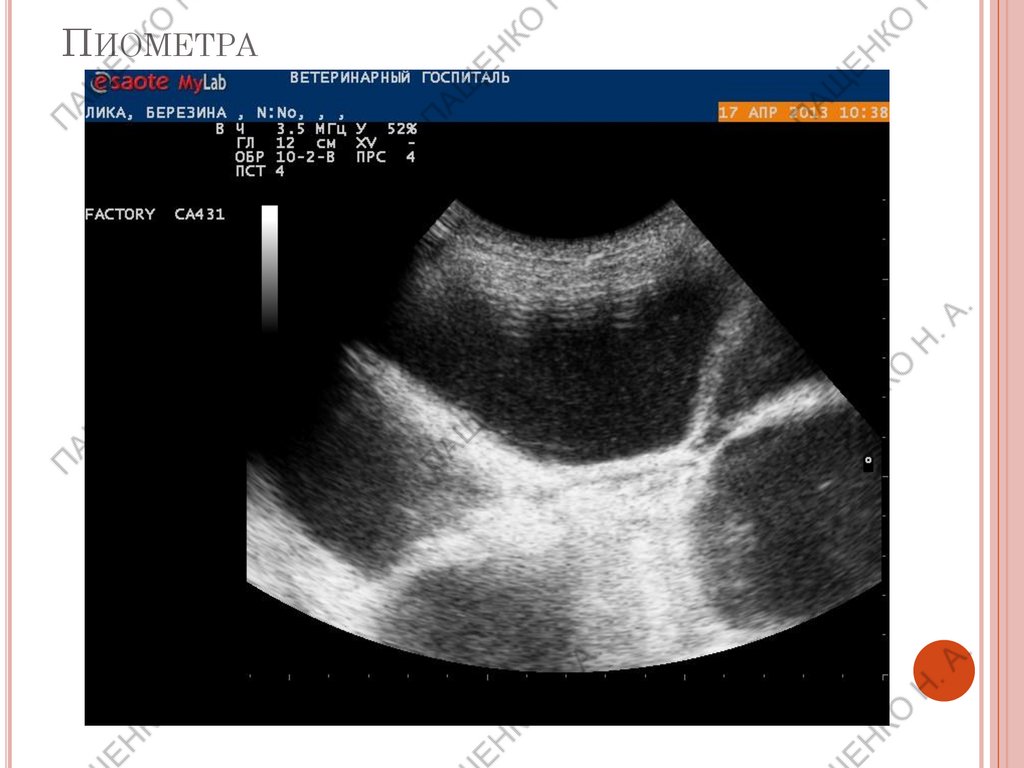

ПИОМЕТРА

ЭКССУДАТИВНЫЕ ПОРАЖЕНИЯ:

К таким поражениям относятся пиометры,

мукометра, гидрометра, гемометра.

В рогах может быть значимая или слабо

выраженная экссудация.

Поражаться могут оба рога, один рог или сегмент

рога.

При наличии взвеси в жидкостном содержимом мы

предполагаем гнойное воспаление или гемометру,

м.б смешанные экссудаты.

При полностью анэхогенном содержимом и тонкой

стенке можно предполагать гидрометру или

мукометру, но только по УЗИ дифференциация не

возможна.

Если вокруг матки выявлено повышение

эхогенности сальника – вероятность гнойного

воспаления очень велика – срочно думать о

возможности перитонита.